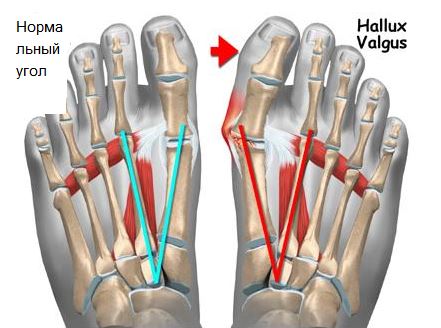

Среди заболеваний стопы наиболее часто встречается плоскостопие. Им страдает до 20% взрослого населения нашей планеты, из которых у 55-60% диагностируется поперечное плоскостопие (шишки на стопах, вальгусная деформация первого пальца или hallux valgus).

Данное заболевание характеризуется прогрессирующим течением. Чаще всего вальгусная деформация большого пальца стопы (hallux valgus) встречается у женщин. Согласно статистике, на одного мужчину, страдающего этим заболеванием, приходится десять женщин. Это может быть связано с генетической или анатомической предрасположенностью женского пола к развитию данного состояния. Но основной причиной такой половой дифференцировки патологии, является форма обуви, которая присуща женщинам – узкие носки и высокие каблуки.